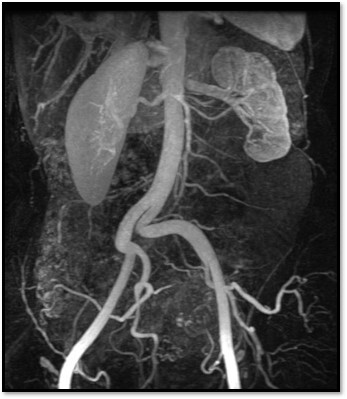

1

Q

What pathology is seen here?

A

Unilateral Renal Agenesis